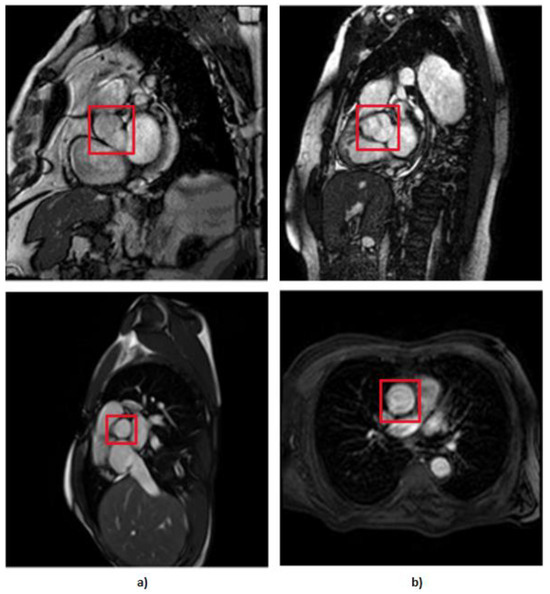

- Recognizing by the cardiology specialist the occasional presence of underexposed images, we addressed this issue by enhancing brightness in the images (Figure 7). By compensating for the darker images, we ensured that our dataset covered a wider spectrum of lighting conditions, thus reinforcing the adaptability of our models. With this technique, we created 404 more MRIs.